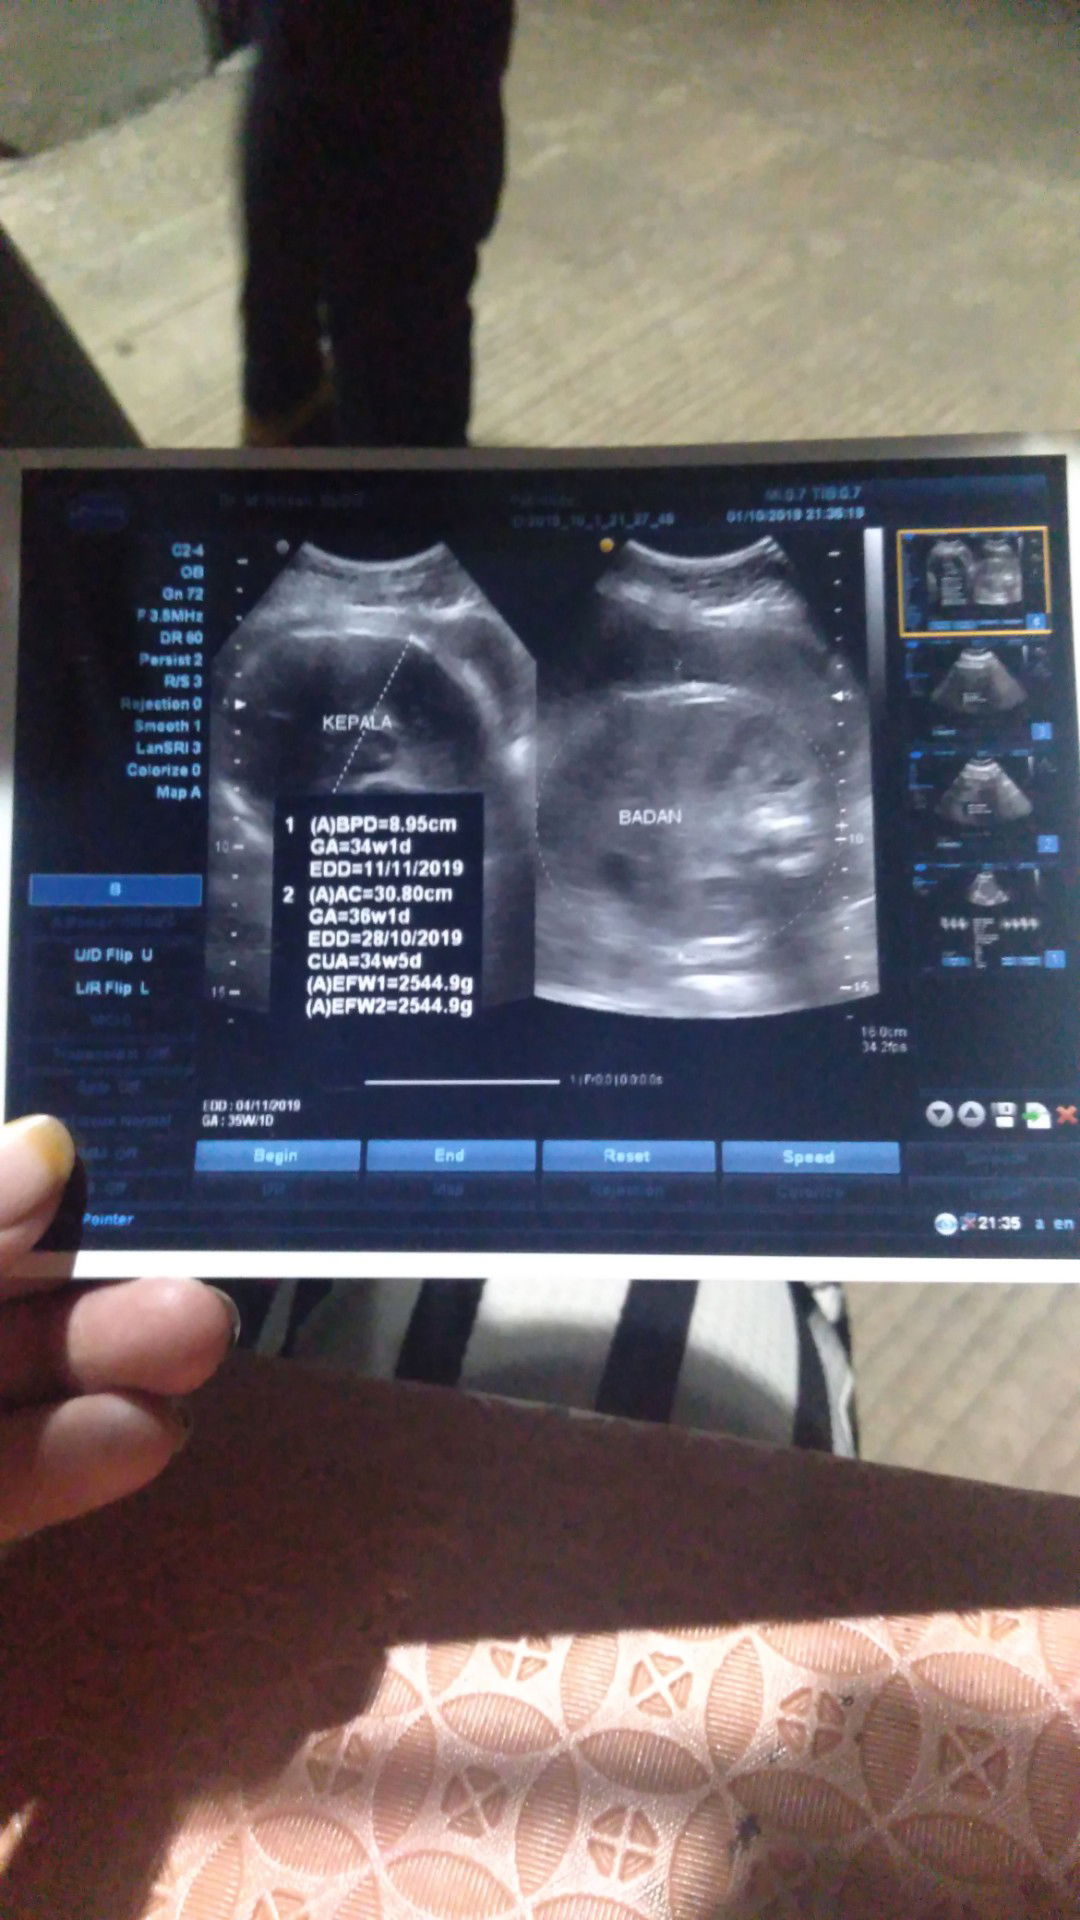

usg

Tadi malam habis usg dan alhamdulilah baby nya sehat dan udah masuk 34w1d dan berat nya 2.5 kilo gram .. dan kta dokternya kurangin mkan bnyak2 takut nya kebesaran pas lahiran .. hhhh gak nyangka udah 2.5 aja soalnya perut ku kyak biasa aja .. dan bahkan kadang2 ngerasa kecil perut nya.. heheheh Doain ya bunda2 cantik lahiran nya normal dan lncar dan juga kedua2 nya sehat .. amin ?????